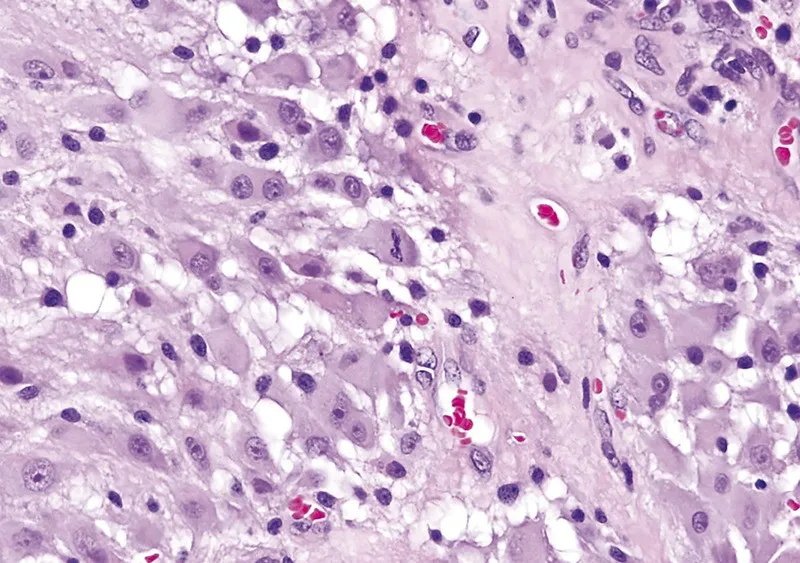

室管膜下巨细胞星形细胞瘤属于边界清楚的星形细胞瘤,属WHO 1级。室管膜下巨细胞星形细胞瘤常为伴发于结节性硬化的少见良性星形细胞肿瘤.占结节性硬化患者的10%~15%,病理学特征为由巨噬细胞样星形细胞构成的室管膜下巨细胞星形细胞瘤与结节性硬化和错构瘤共存。肉眼所见肿瘤为边界清楚的分叶状肿块,常见钙化、囊变和丰富的血管。镜下典型者呈双核或多核星形细胞瘤,常见囊变,分化良好,可见两核或多核形成,有丝分裂少见。

CNS WHO 1级命名不因有丝分裂活性(A)、少见的微血管增生(B)或坏死(即使栅栏状)(C)而改变。

CNS WHO 1级命名不因有丝分裂活性(A)而改变。

CNS WHO 1级命名不因少见的微血管增生(B)而改变。

CNS WHO 1级命名不因坏死(即使栅栏状)(C)而改变。